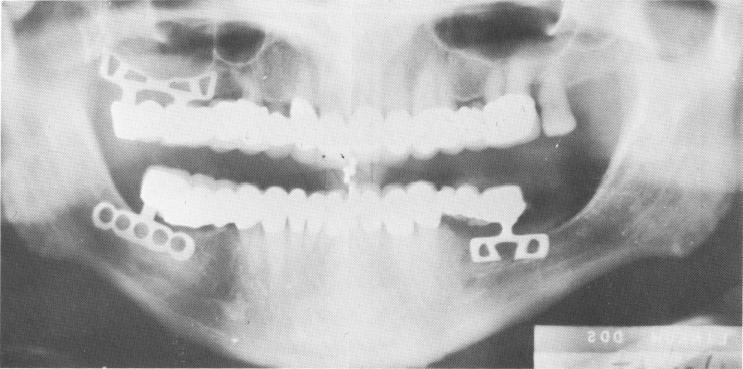

A final Panorex shows the mandibular and maxillary blade-vents in the bone (Fig. 11-58).

Fig. 11-58. A postoperative Panorex. Implants were also used bilaterally in the posterior areas of the mandible.